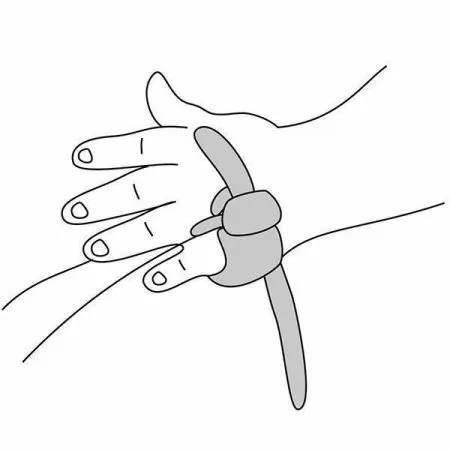

Датчик детский (манжета) |

1 |

Датчик пульсоксиметрический пальцевой |

1 |